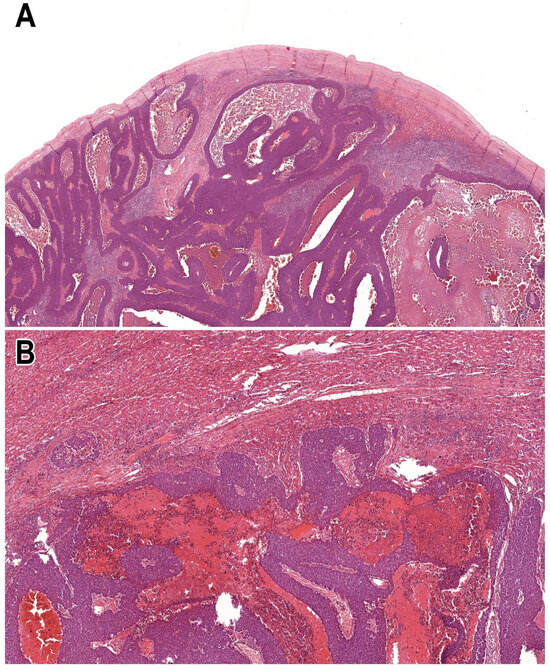

Hematoxylin and eosin (H&E)-stained histological slides were retrieved from the archives of the Department of Pathology. Slides containing only tumour tissue without adjacent tumour-free liver parenchyma were excluded. Additionally, subcapsular metastases were omitted, as these lesions may exhibit a ‘pseudo-desmoplastic’ pattern that could confound accurate HGP assessment (Figure 1). All metastatic foci within each case were evaluated individually.

Figure 1.

Microscopic features of subcapsular metastasis of gallbladder neuroendocrine tumour, resulting in ‘pseudo-desmoplastic’ pattern ((A); HE, 2×), while the rest of the tumour reflected pushing pattern ((B); HE, 5×).